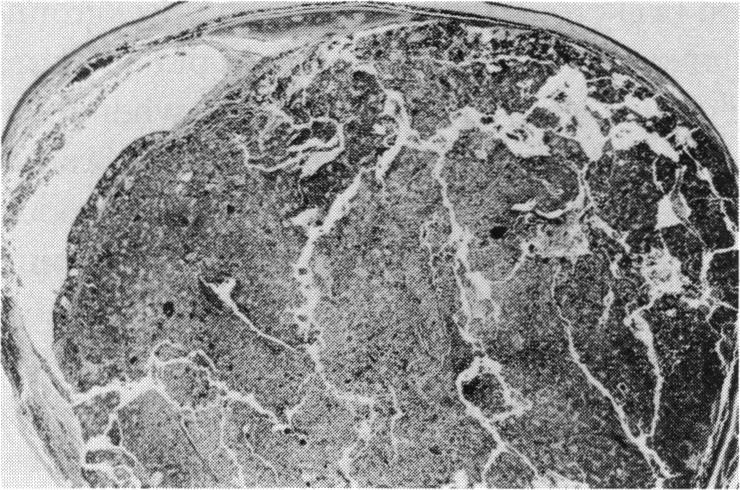

Transgenic models of retinoblastoma: what they tell us about its cause and treatment.

Trans Am Ophthalmol Soc. 1994;92:385-400; discussion 400-1.

PMID:7886874

原文链接:https://pmc.ncbi.nlm.nih.gov/articles/PMC1298518/